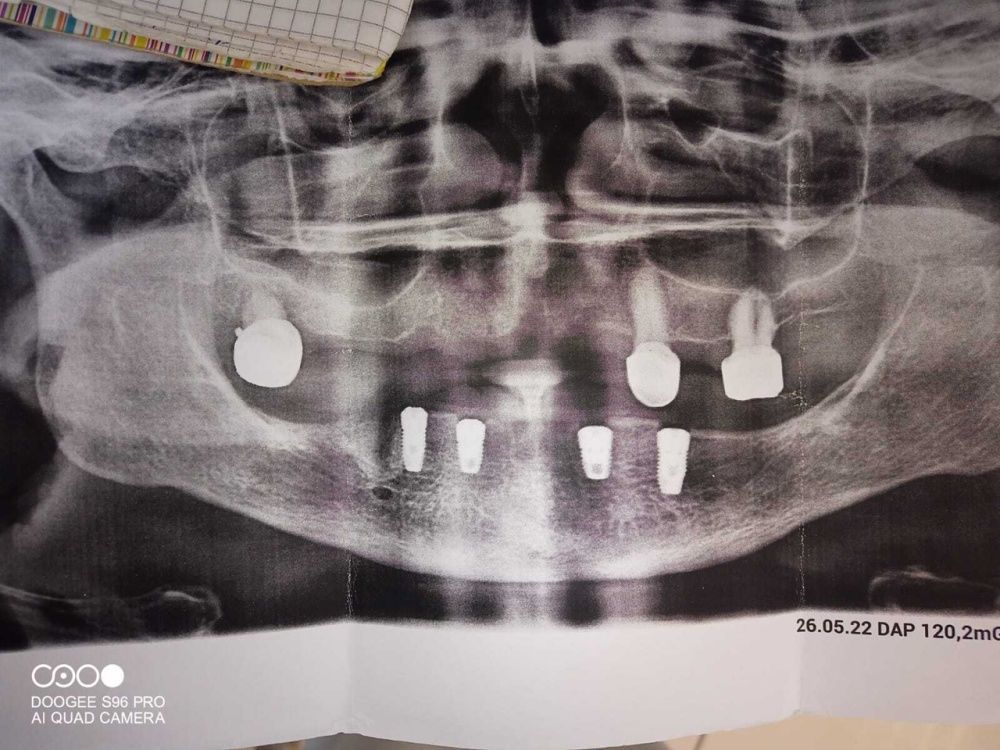

К нам в клинику, к доктору Шаймарданову Ф.Т., обратилась пациентка И. с жалобами на полное отсутствие зубов в нижней челюсти и невозможность ношения полного съемного пластинчатого протеза, так как он не фиксируется на нижней челюсти. Врач предложил установить 4 имплантата в нижнюю челюсть с дальнейшим протезированием балочной системы условно съемного пластинчатого протеза с опорой на имплантаты. Такой протез хорошо фиксируется на имплантатах и обеспечивает удобные условия для гигиены полости рта и протеза.